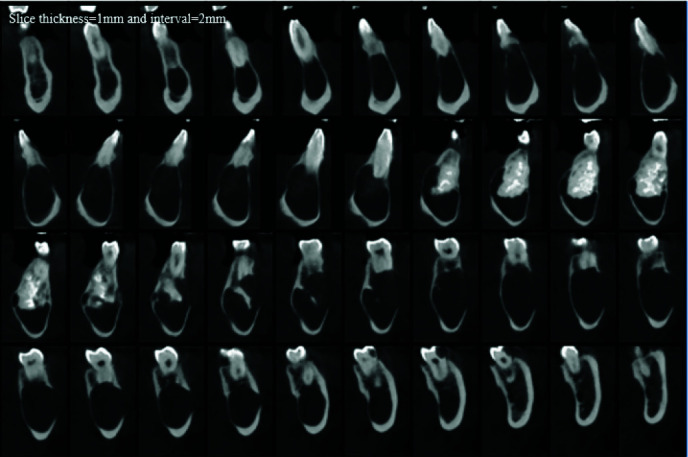

Hybrid lesions of jaws are rare entities defined as two different lesions co-occurring in the same location, with identical histopathological origin. Ameloblastoma, calcifying cystic odontogenic tumor and odontoma are among the most common lesions that have been reported to combine with other lesions. In this study, a hybrid lesion of odontogenic keratocyst (OKC) and odontoma in the mandible of a forty-five years old male reported. Additional to the rarity of this hybrid lesion, the present case had unique radiologic features, including atypical location and extension of the lesion and profound knife-edge root resorption of the teeth in the area, which was not a common feature for any of the two lesions. The surgical procedure was marsupialization to reduce the size of the lesion. As a result of the surgery, the healing of the surgical wound was uneventful. In addition, careful follow-up for the patient was conducted, which had no recurrence till now (after 15 months).